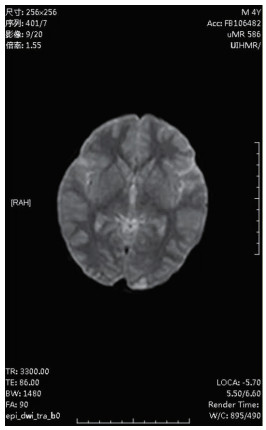

| 图 1 2月18日头部CT |

图 1为颅内弥漫脑实质肿胀,脑沟脑回显示不清,脑室受压,部分脑沟内可见高密度影,右侧小脑幕密度增高。中线结构居中。副鼻窦内见软组织密度影。图 2为大脑皮层、小脑及脑干形态肿胀,呈稍长T2信号影,有类似束带征。图 3为后颅窝去骨辨减压+小脑部分切除术后复查: 脑疝征象明显好转。